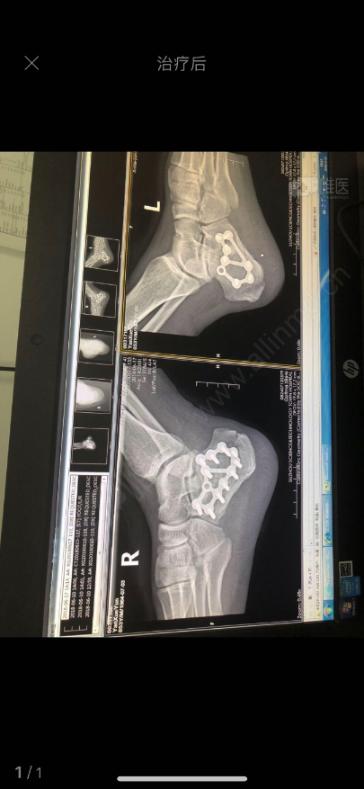

跟骨骨折切开复位钢板内固定术

病例讨论跟骨骨折

29岁跟骨骨折闭合撬拨复位内固定手术一例